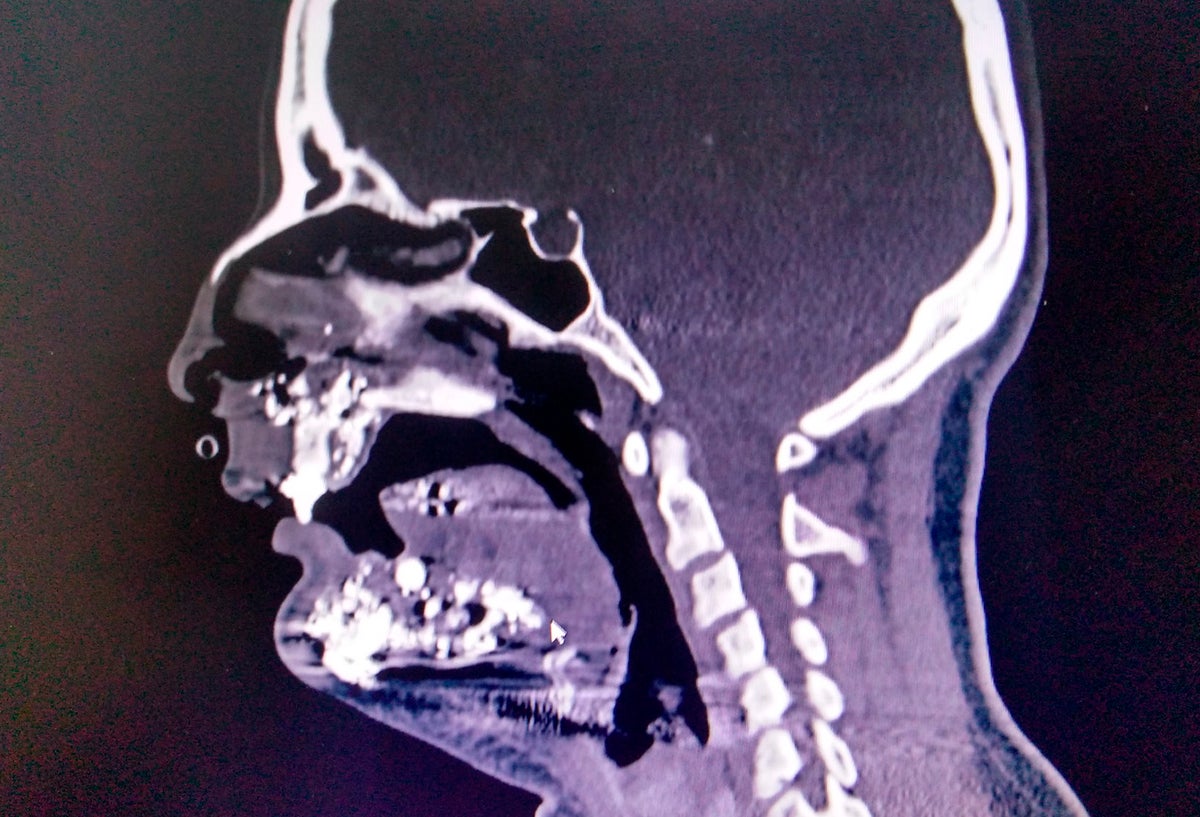

Los daños que sufrió la mujer

Los daños que sufrió la mujer Crédito: Imagen suministrada a LA FM y RCN Radio

En el sur de la capital de la República, en la localidad de Usme, una mujer de 30 años madre cabeza de familia fue víctima de un intento de asalto, en el que el delincuente le disparó tres veces en su rostro causándole serias lesiones.

Se trata de María Marcela González, quien una vez recibió los impactos de bala, fue remitida al Hospital de Meissen en donde fue sometida a varias cirugías y a una completa reconstrucción facial que permitió que se salvara su vida milagrosamente.

González agradeció a los médicos que participaron en la intervención quirúrgica que duró cuatro horas, en la que los especialistas lograron salvar su vida luego de estar al borde de la muerte por la profundidad de las heridas.